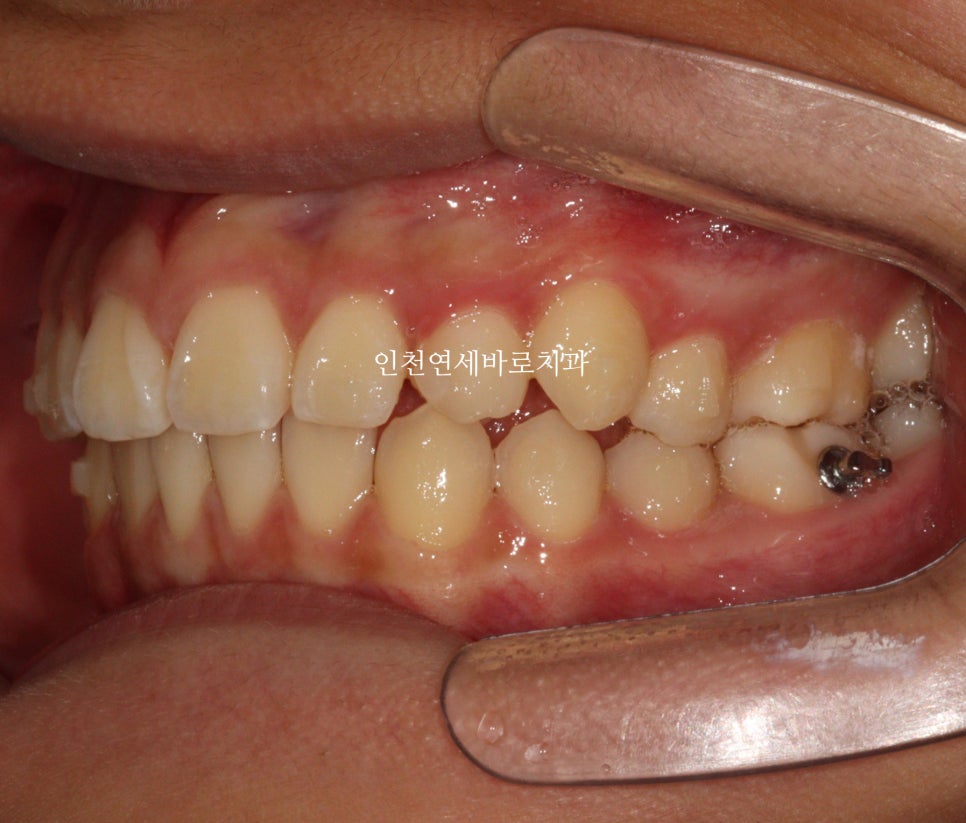

첫 셋트가 끝났을 때 모습입니다.

위에 있던 치아는 자연맹출을 유도했는데 꽤나 그럴싸한 배열이네요

마무리를 간단하게 시작합니다.